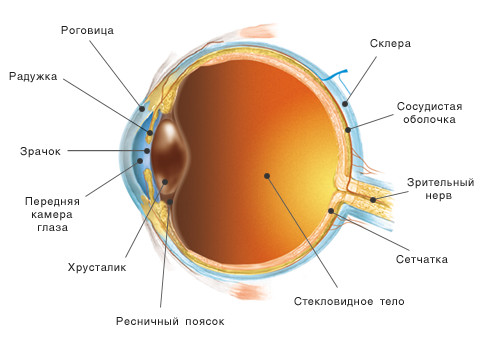

КТ-графики и изображение строения глаза